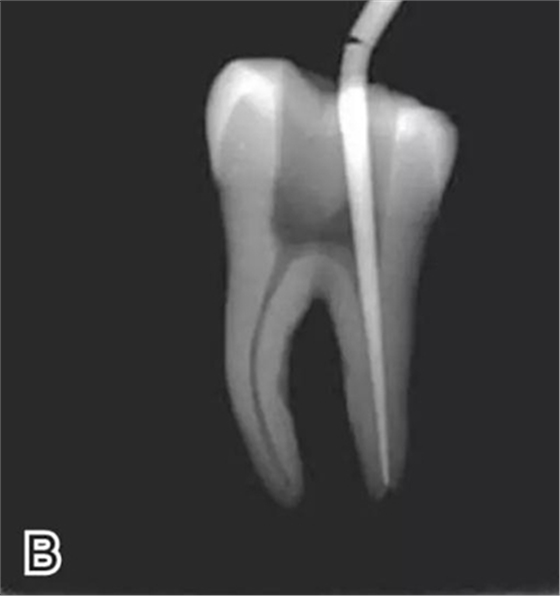

要求工作尖能自由到達(dá)距根尖4~5 mm(有學(xué)者提出3~4 mm)的位置并能輕微接觸根管壁,用橡皮片做好標(biāo)記(圖1)。

圖1 選擇攜熱器工作尖,A.試攜熱器尖 B.工作尖在根內(nèi)的位置